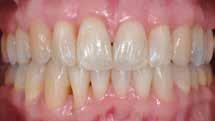

I samråd med patienten og egen tandlæge* afstemmes forventningerne, inden der bestilles refinement alignere. Nivelleringen af alle tænder i tandbuerne, smilelinje og -kurve samt den bukko-lingvale position af incisiverne foretages og efterfølges af retainers lingvalt på over- og underkæbeincisiver (Fig. 3 A-D). Hele behandlingen udføres under løbende kommunikation med patient og egen tandlæge*, der udfører den efterfølgende rekonstruktion med direkte plast (Fig. 4 A-D). Behandlingsvarigheden har været to år og to måneder, hvor ortodontien har forløbet over 21 måneder. Der har været anvendt et første sæt på 66 alignere samt yderligere to sæt med ni refinement alignere. Tandblegning og direkte plastrekonstruktion er udført af egen tandlæge* (Fig. 5 A-F).

Fig. 5. A, B. Smil og kæbeforhold før og efter. Et bredere smil med korrektion af de laterale mørke rum. C-F. Harmonisk hældning af overkæbe- og underkæbeincisiver, rekonstruktion af den tabte tandsubstans efter nivellering af gingivaniveau og optimal bukko-lingval placering til direkte plastbehandling.

5. A, B. Smile and jaw relationships before and after. A wider smile with correction of the lateral dark spaces. C-F. Harmonious inclination of the upper and lower jaw incisors, reconstruction of the lost tooth substance after leveling the gingival level, and optimal bucco-lingual positioning for direct plastic treatment.